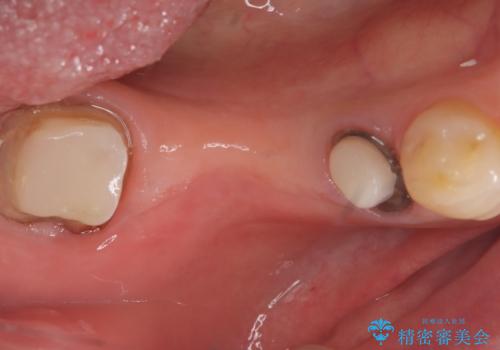

- 主訴:つい先日入れたセラミック(ジルコニア)ブリッジが奥歯部分で割れた。いつも同じ場所で壊れる。これで3度目。

セラミックに比べ、割れづらい金属(ゴールドでのブリッジのやり替えとなりました。

セラミックに比べ、破折リスクの少ない金属を使用したブリッジでのやり替えとなりました。

両支台歯が失活歯のため、どちらかもしくは両方の歯が破折した際、再度ブリッジを除去した治療が必要になるリスクとインプラント治療のご提案もさせていただきましたが、ブリッジでの治療を希望されました。

右下5番は支台歯CR築造を行っています。